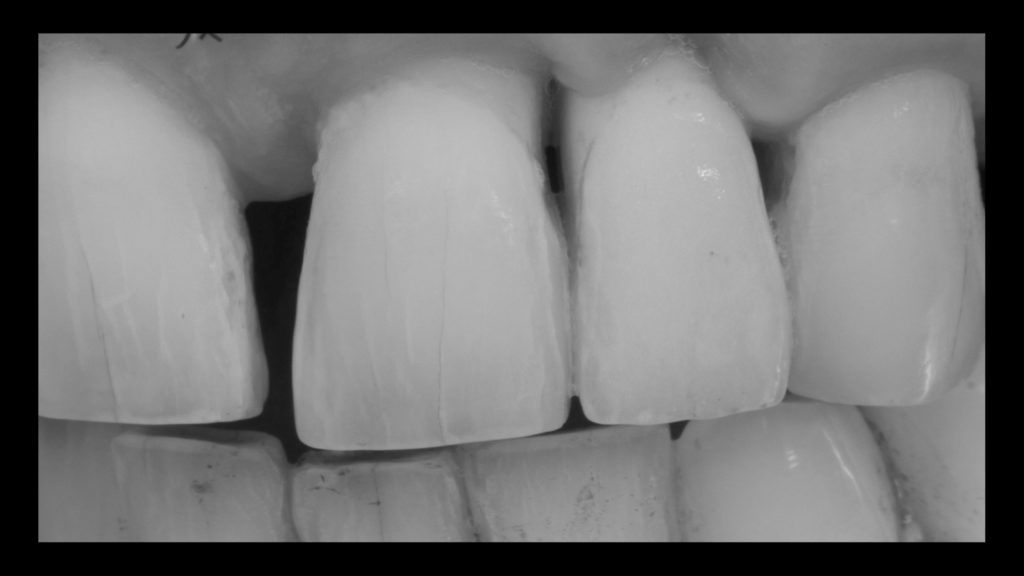

Die Implantatkrone sollte metallkeramisch gelöst werden, was wiederum bedeutete, dass für die entsprechend designte Implantatkrone ein CAD/CAM-gestützt gefertigtes Abutment (vorgefertigt, Schweden & Martina) mit einer Metallkeramik (Ceramco 3, Dentsply Sirona) verblendet werden musste. Es wurde eine zementierte Lösung gewählt, weshalb es keinen Schraubenkanal gab und somit keine Probleme mit dessen Austritt gelöst werden mussten. In den Abbildungen 6a und 6b sind die DSLR-Aufnahmen des Behandlers dargestellt. Die Referenzfarbmuster vermitteln die ungefähre Zahnfarbe, aber nicht alle Informationen und Merkmale, die für die Rekonstruktion des natürlichen Zahns vonnöten sind. Indem man die Belichtung reduziert und den Kontrast sowie die Brillanz in einem Bildbearbeitungsprogramm wie Lightroom (Adobe) erhöht, lässt sich die Histoanatomie des natürlichen Zahns besser darstellen (Abb. 6c).

Auf Wunsch des Patienten sollte der zu rekonstruierende laterale Schneidezahn die Charakteristika des mittleren Inzisiven 21, also seines direkten Nachbarzahns aufweisen. Normalerweise hätte man sich an dem noch verbliebenen lateralen Schneidezahn im ersten Quadranten orientiert, doch leider war auch dessen Zustand nicht ideal, sodass auch dieser in Bälde rekonstruiert werden sollte (Abb. 7a und b). Bei der eingehenden Betrachtung des Zahns 21 stellten wir zwar eine gewisse Ähnlichkeit mit den vom Zahnarzt gewählten Farbmusterzähnen fest, erkannten aber auch relevante Unterschiede. Aus diesem Grund starteten wir die laborseitige Analyse mit polarisierten Aufnahmen (Abb. 8a und b). Da der Patient 49 Jahre alt war, suchten wir gezielt nach charakteristischen Merkmalen natürlicher älterer Zähne und und wurden auch fündig.

Rohbrandeinprobe

Bei der Rohbrandeinprobe stellten wir einen leichten Helligkeitsunterschied zwischen der Restauration und unserem Referenzzahn 21 fest. Am auffälligsten zeigte sich diese Abweichung insbesondere am inzisalen Drittel und an den Rändern (Abb. 30a bis c). Zur Dokumentation der Farbabweichung und dezidierten Farbauswahl wurden daher im Rahmen der Rohbrandeinprobe nochmals Fotos angefertigt. In diesem Fall kamen die Farben B4, A4 und D2 den natürlichen Zähnen am nächsten. Und auch der zuvor gewählte Schmelz musste aufgrund der falschen Helligkeit und Transluzenz verändert und die Effekte im inzisalen Drittel verstärkt werden (Abb. 31a bis c). Insbesondere die Leuchtkraft und Transluzenz, aber auch die Transluzenz und Sättigung des rot-orangen Opaleszenz-Effekts im Bereich der Mamelons des natürlichen Zahnschmelzes sowie die „gefürchteten“ Schmelzrisse wussten zu beeindrucken und galt es bei der Rekonstruktion zu beachten.